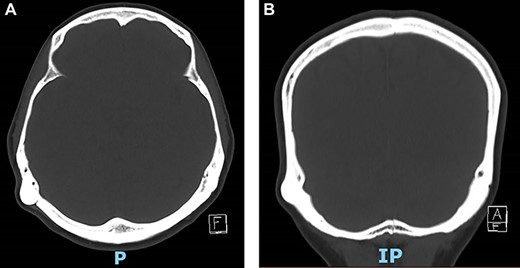

X-ray skull AP & lateral views (Fig. 1) did not show bony erosions, lytic lesions or sclerotic lesions which if present would indicate a possible infectious, inflammatory or neoplastic process. However, the bony swelling was difficult to assess on X-ray due to orientation.

A relatively normal X-ray skull which did not show any significant pathology.